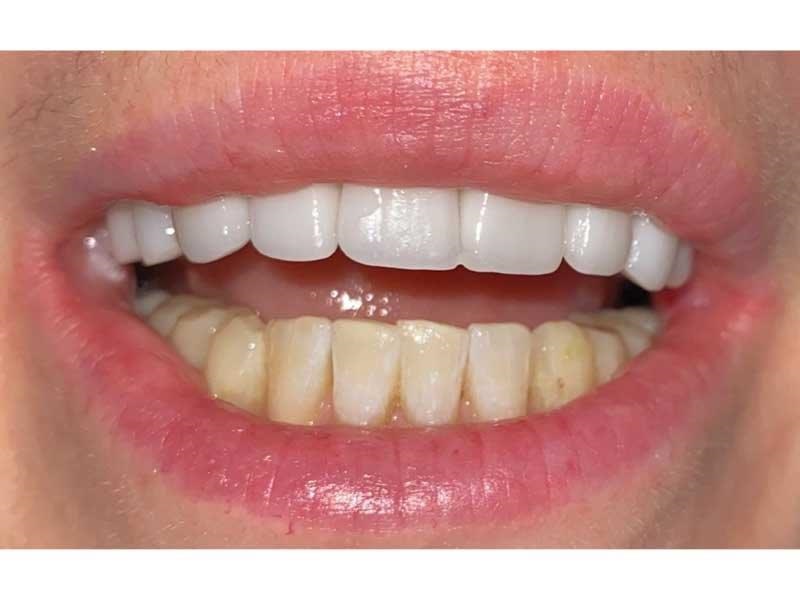

Meet Lorraine, who came into my office to “redo her bonding.” Lorraine had some upper anterior teeth done years ago with resin, which now was dull, stained and breaking down (Figs. 1–3). She had an amount of money in mind that she thought it would cost. She was very wrong.

Fig. 1

Fig. 2

Fig. 3